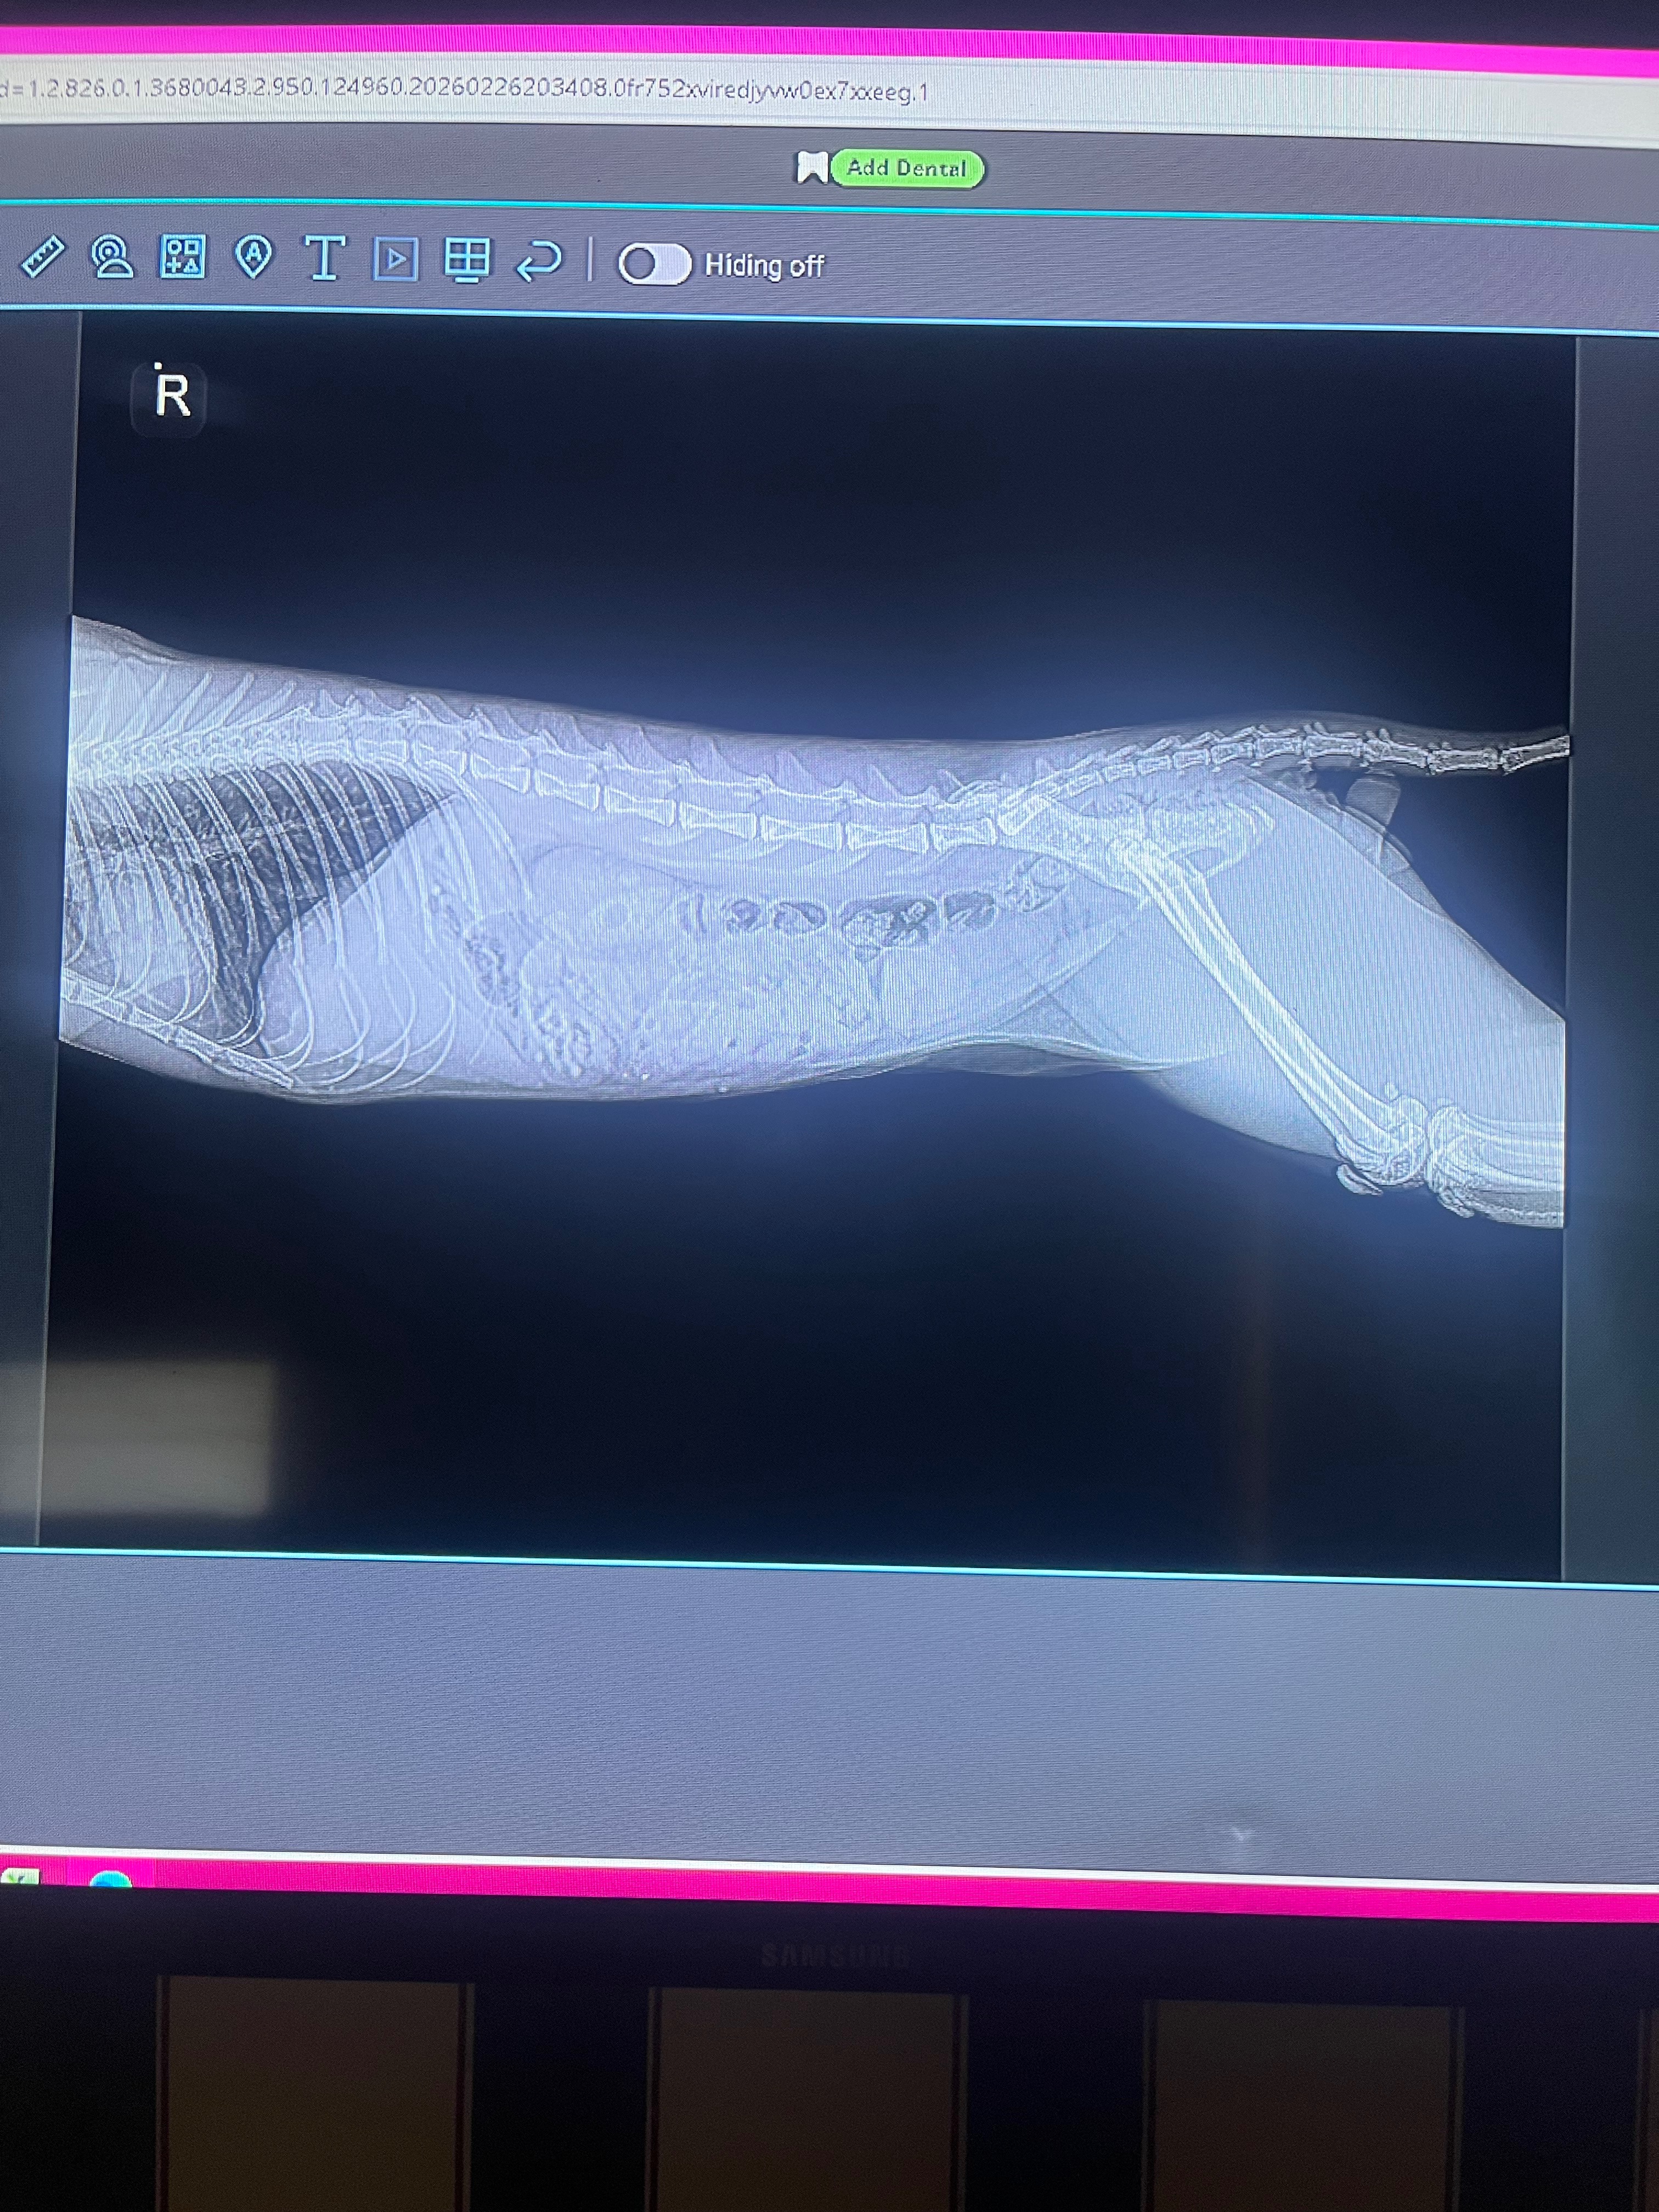

The X-Ray Came Back, And It Wasn’t Good. Kage Was Completely Blocked. His Stomach Was Full Of Hair Ties, And All Kind Of Other Things He Might’ve Swallowed Like Food, Hair, ETC. They Were Beginning To Bunch Up Because Of How Long They Were In There, Getting Stuck In His Small Intestines. The Next Step Was To Send The X-Rays To A Radiologist Who Could Confirm Exactly What He Needs, But It Most Likely Meant He Needed Surgery.

His Family Was Now At A Loss. They Couldn’t Afford To Get The Next Step He Needed To Recover. They Sadly Had To Take Kage Back Home With Nothing But A Prayer That He’d Be Okay Until They’d Be Able To Get More Money To Get The Next Step He Needs To Feel Better. All They Had Were X-Ray Photos, And A Medication That The Hospital So Kindly Gave Them To Maybe Help In Any Way Possible.